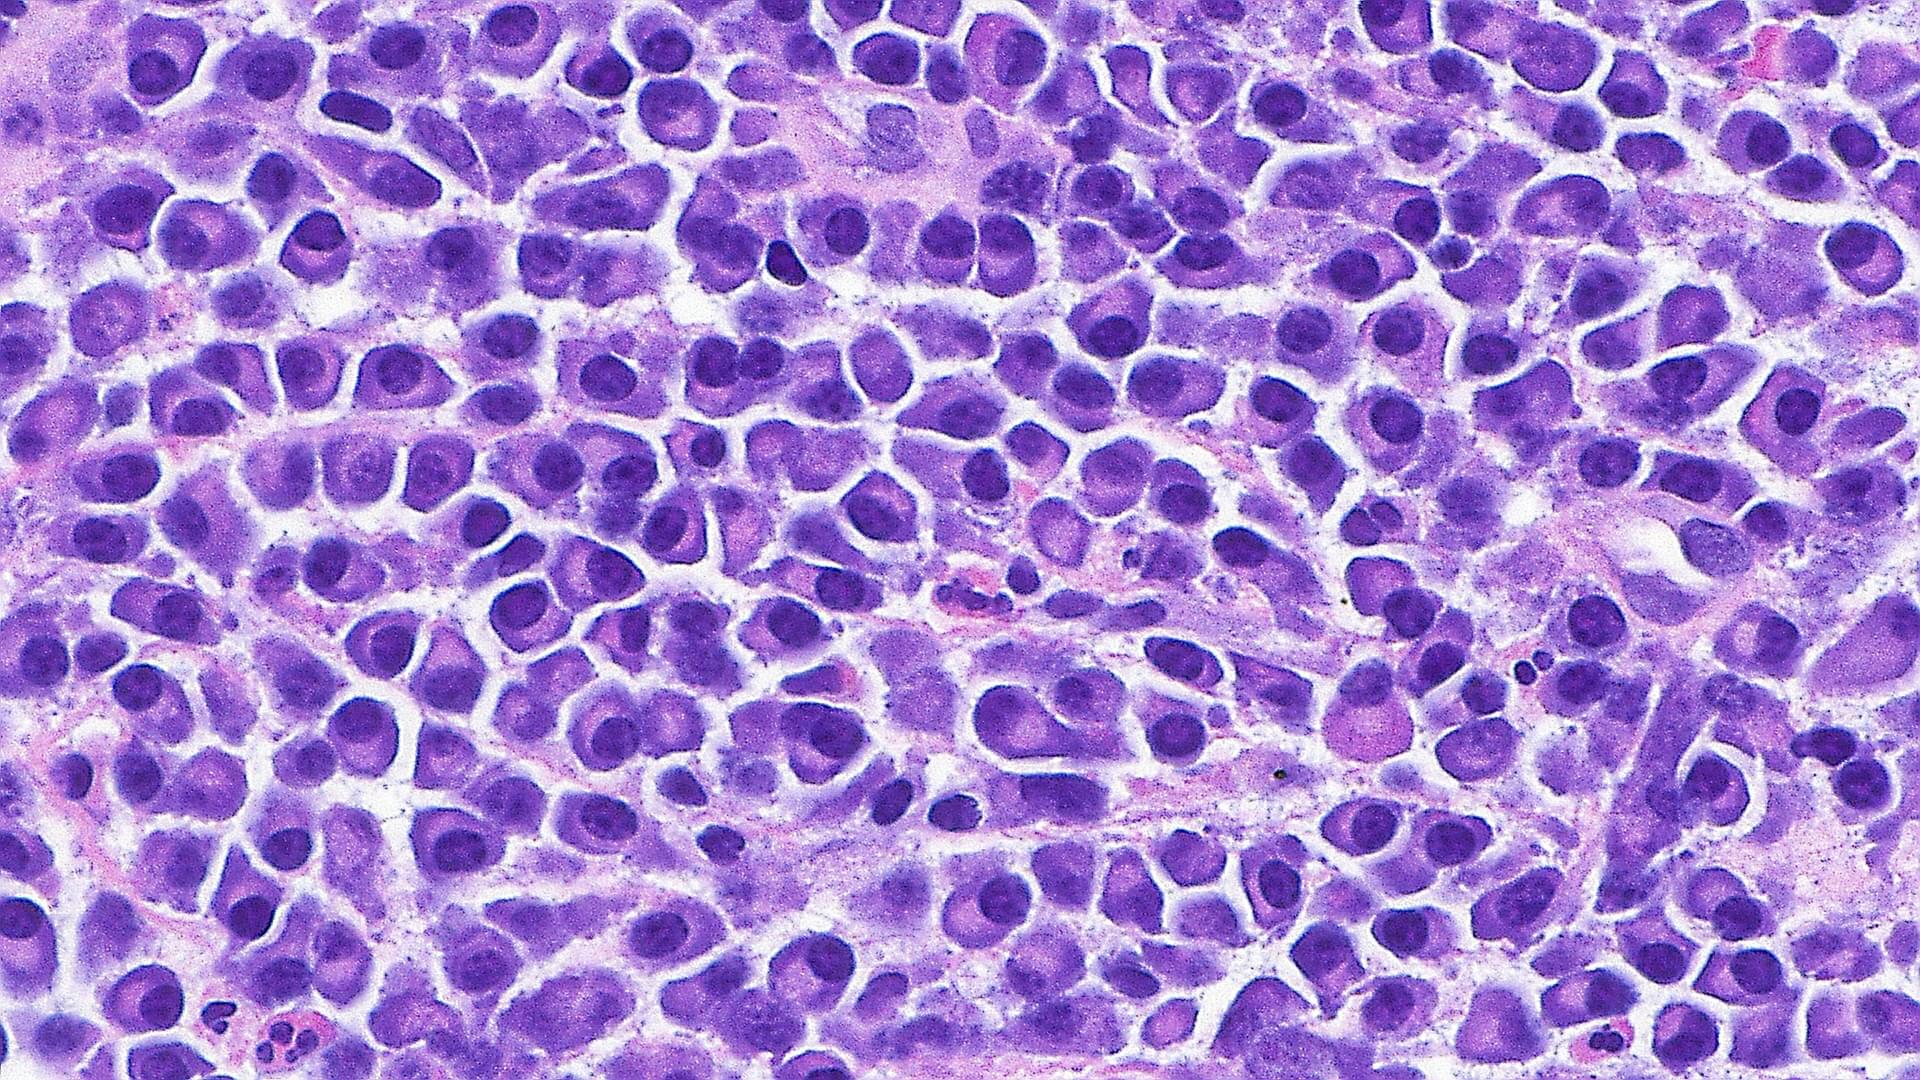

Temporal lobe epilepsy, which results in recurring seizures and cognitive dysfunction, is associated with premature aging of brain cells.

A new study by researchers at Georgetown University Medical Center found that this form of epilepsy can be treated in mice by either genetically or pharmaceutically eradicating the aging cells, thereby improving memory and reducing seizures as well as protecting some animals from developing epilepsy.

The study appears in the journal Annals of Neurology.